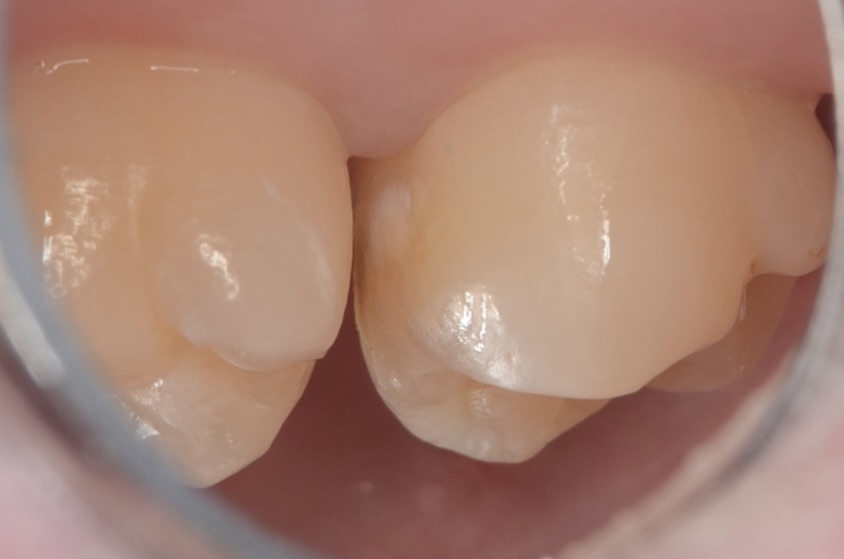

20代 虫歯治療 VPT(歯髄温存療法)ダイレクトボンディング #36

Before

After

| 年齢 | 20代 | 治療方法 | VPT(歯髄温存療法)/ダイレクトボンディング |

| 性別 | 女性 | 通院回数 | 2回 |

| 主訴 | むし歯を治したい /神経を取りたくない/できるだけ神経を取りたくない | 費用 |

170,500円(税込) |

| 治療のメリット | 神経を保存できる。歯を削る量を少なくできる。自然な形にできる | ||

| 治療のデメリット | 神経を保存できない場合がある。 | ||